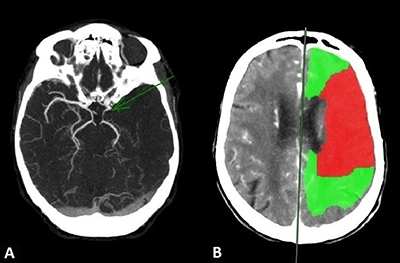

Non-contrast CT (NCCT), CT-angiography (CTA), and CT-perfusion (CTP) were thereafter performed for angiographic assessment including carotid arteries, circle of Willis, and intracranial collateral circulation (Figure 2). NCCT showed loss of differentiation between grey matter and white matter in the left MCA territory and acute thrombotic hyperdensity within the MCA. CTA showed proximal occlusion of the left MCA (Figure 2A) and CTP showed a perfusion mismatch between infarcted core (Figure 2B, red area) and peripheral hypoperfusion (Figure 2B, green area) featuring the ischemic penumbra (Figure 2B).

Figure 2

(A) CTA image showing proximal occlusion of the left MCA (green arrow) and (B) CTP image showing a mismatch between the infarcted core in red and the peripheral hypoperfusion in green.